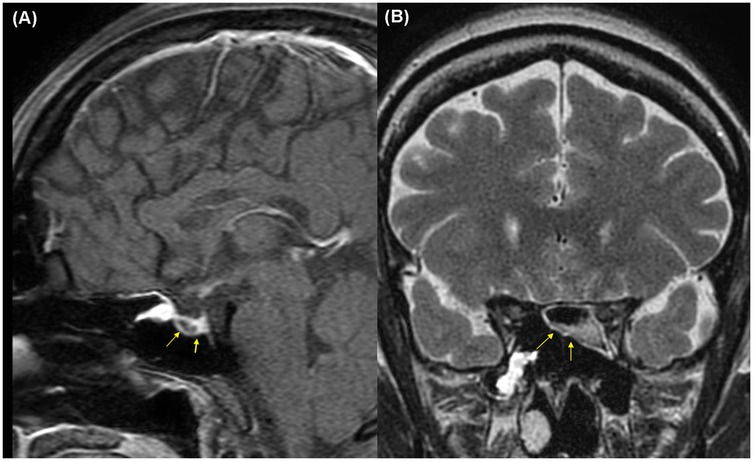

This report was approved by the Institutional Review Board (IRB) of our institution (HC25ZISI0005), and written informed consent was obtained from the patient. A 32-year-old woman at 37 weeks and 6 days of gestation underwent an elective cesarean section for breech presentation, complicated by massive PPH resulting from uterine atony. The hemorrhage rapidly progressed to hemorrhagic shock and culminated in cardiac arrest. After 20 min of resuscitation, spontaneous circulation was restored, and an emergent hysterectomy was performed. The patient was transfused with 68 units of red blood cells, 80 units of fresh frozen plasma, and 77 units of platelets, along with the infusion of 6,000 ml of crystalloid intraoperatively. Estimated blood loss was approximately 20 L. Upon admission to the intensive care unit, the patient remained in profound shock with ongoing hemorrhage, prompting immediate referral to the acute care surgery department for definitive management of her hemodynamic instability. The patient demonstrated refractory hypoperfusion despite comprehensive organ support, including mechanical ventilation, renal replacement therapy (RRT), and the administration of vasopressors and inotropes at maximal doses. Ongoing hemorrhage was evident through the surgical drain, accompanied by progressive abdominal distension. Consequently, an emergent laparotomy was performed the day after delivery, revealing persistent bleeding from the right adnexa, which was controlled with suture ligation. After surgery, the patient demonstrated a marked improvement in hemodynamic and perfusion parameters (Figure 1), facilitating the cessation of vasopressors on postoperative day (POD) 2, RRT on POD 3, and successful liberation from mechanical ventilation by POD 4. On POD 6, the patient was transferred to the general ward, continued oral feeding, and maintained clinical stability. However, on POD 8 (postpartum day 9), the patient acutely developed delirium, hyperpyrexia peaking at 41°C, tachypnea, and tachycardia. A comprehensive fever workup revealed normal inflammatory markers, including C-reactive protein and procalcitonin, no radiographic evidence of pneumonia, and no significant abnormalities in laboratory investigations, including electrolytes, resulting in considerable diagnostic uncertainty. Nevertheless, based on clinical judgment, a psychotic disorder related to critical illness was empirically suspected, and treatment with antipyretics and haloperidol was initiated; however, these interventions ultimately failed to yield improvement. On that day, despite unremarkable findings on neurological examination and a lower likelihood of bacterial meningitis, the absence of viable treatment options and the critical need to exclude potential life-threatening conditions necessitated prompt initiation of magnetic resonance imaging (MRI) of the brain and cerebrospinal fluid analysis. Simultaneously, empirical treatment with broad-spectrum antibiotics and an intravenous infusion of dexamethasone 10 mg was commenced. Following initiation of treatment, the patient demonstrated rapid and marked clinical improvement, achieving normothermia, restored alertness, and hemodynamic stability by POD 10. Brain MRI demonstrated hypointensity of the anterior pituitary lobe on both sagittal T1-weighted (Figure 2A) and coronal T2-weighted images (Figure 2B). Following gadolinium administration, the gland exhibited peripheral rim enhancement with central non-enhancement, a radiological pattern consistent with acute hemorrhagic necrosis of the adenohypophysis. In light of the clinical course and imaging findings, SS was strongly suspected, and the patient's significant recovery was thought to be attributable to the effects of steroid therapy rather than broad-spectrum antibiotics. Accordingly, hormonal studies were performed to confirm the underlying diagnosis, revealing significant abnormalities in the hypothalamic-pituitary-growth, gonadal, and lactotrophic axes, while thyroid function remained intact, as demonstrated by triiodothyronine, free thyroxine, and thyroid-stimulating hormone levels of 87.52 ng/dl (reference: 80–200 ng/dl), 13.11 pg/ml (reference: 8–20 pg/ml), and 0.90 mIU/L (reference: 0.4–4.0 mIU/L), respectively. The growth axis dysfunction was reflected by a markedly reduced insulin-like growth factor-I level of 78.63 ng/ml (reference: 115–358 ng/ml), while gonadal axis abnormalities were characterized by profoundly low levels of follicle-stimulating hormone at 0.19 mIU/ml (reference range in reproductive age women: 3.5–12.5 mIU/ml, variable by menstrual cycle phase) and estradiol at 1.0 pg/ml (reference range in reproductive age women: 30–400 pg/ml, variable by menstrual cycle phase), with luteinizing hormone at 1.02 mIU/ml, which is inappropriately low for the hypoestrogenic state (reference range in the follicular phase: 2.4–12.6 mIU/ml), consistent with central hypogonadism. Moreover, the lactotrophic axis displayed an inappropriately low prolactin level of 5.17 ng/ml (reference range in pregnancy: typically >100–200 ng/ml). Although the serum cortisol concentration was measured at 20.33 μg/dl (reference range at 8 AM: 5–25 μg/dl), this value should be interpreted with caution. It may have been transiently influenced by the initial administration of hydrocortisone; however, it is also important to note that pregnancy, particularly in the third trimester, is characterized by markedly elevated circulating estrogen levels that increase corticosteroid-binding globulin concentrations, leading to a two- to threefold rise in total cortisol compared with nonpregnant individuals. Therefore, the measured cortisol level in this patient is relatively low for the expected gestational state. In addition, the adrenocorticotropic hormone (ACTH) level (20.6 pg/ml, reference: 10–60 pg/ml), while technically within the normal range, was considered inappropriately low in the context of acute physiologic stress. Collectively, these findings indicate a multifaceted endocrine dysfunction with preservation of thyroid function. During the hospitalization, the patient underwent a gradual tapering of steroid therapy, which was successfully discontinued prior to discharge on POD 17. She was unable to breastfeed after delivery, exhibiting postpartum agalactia, a hallmark clinical manifestation of SS. Subsequently, the patient has been under regular follow-up care with the endocrinology department and remains off any hormonal replacement therapy (HRT) at present. At approximately 31 months postpartum, reassessment demonstrated thyroid function, ACTH, and cortisol levels within normal ranges. Menstrual cycles had not resumed at that time, and hormonal evaluation indicated that the gonadotropic axis remained unrecovered.

Figure 2. Brain magnetic resonance imaging on postpartum day 9 demonstrating hemorrhagic necrosis of the pituitary gland (yellow arrows): (A) sagittal T1-weighted image, (B) coronal T2-weighted image.